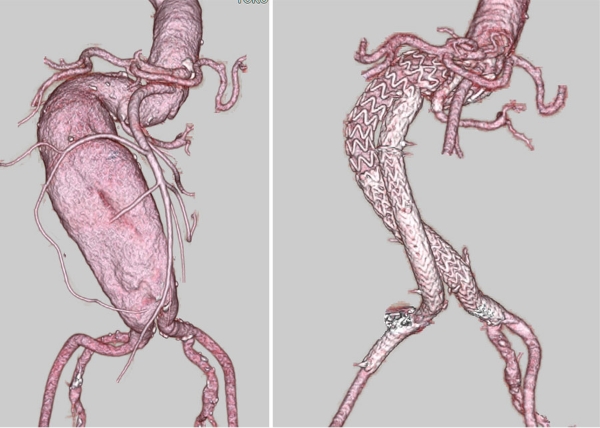

81歳男性、21年前の冠動脈バイパス術3枝(左内胸動脈-左前下行枝, 大伏在静脈-左回旋枝, 大伏在静脈-右冠動脈)および15年前の腹部大動脈瘤人工血管置換術後の患者で、5年前にB型大動脈解離を発症し以後、胸部大動脈拡大をフォローされていた患者さんです。

経時的に拡大傾向は持続し、最大径で63mmとなり破裂のリスクがあるものの、Japan scoreという評価指標で予測術後死亡率が57.3%とリスクが高いため別の病院で手術を断られたものの、何とか治療してほしいと当院を受診されました。

大動脈瘤としては弓部から下行、胸腹部移行部までの広範囲のものであること、同時に腎機能低下(Cr1.49)、呼吸機能障害(%VC60.6、1秒量1.33L)、陳旧性心筋梗塞による心機能低下(EF43%)および左内胸動脈-左前下行枝バイパスグラフト開存症例であることからグラフト損傷しないように治療戦略を熟慮する必要がありました。

当科としては決定したプランは、下行中位から遠位の瘤が最大であるため、まず同部位に対しTEVARを先行しました。

次いで、再胸骨正中切開にて全弓部置換術およびオープンステントグラフト内挿術を施行しました。

再手術に習熟したスタッフで左内胸動脈グラフトを丁寧に剥離、同定。損傷することなく対処することが出来ました。

最後にオープンステントグラフトと初回のステントグラフトをつなげるようにTEVARを行い、弓部から胸腹部移行部までの広範囲胸部大動脈瘤の治療を完了しました。

ハイリスク症例ではありましたが合併症なく独歩退院となり現在は外来フォローアップ中です。